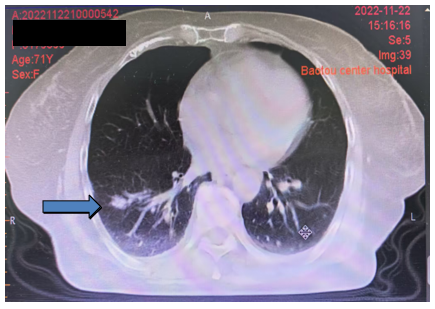

2022年11月22日复查胸腹部CT:双肺多发结节灶考虑转移,较前略缩小(图1)。疗效评价:部分缓解(PR)。